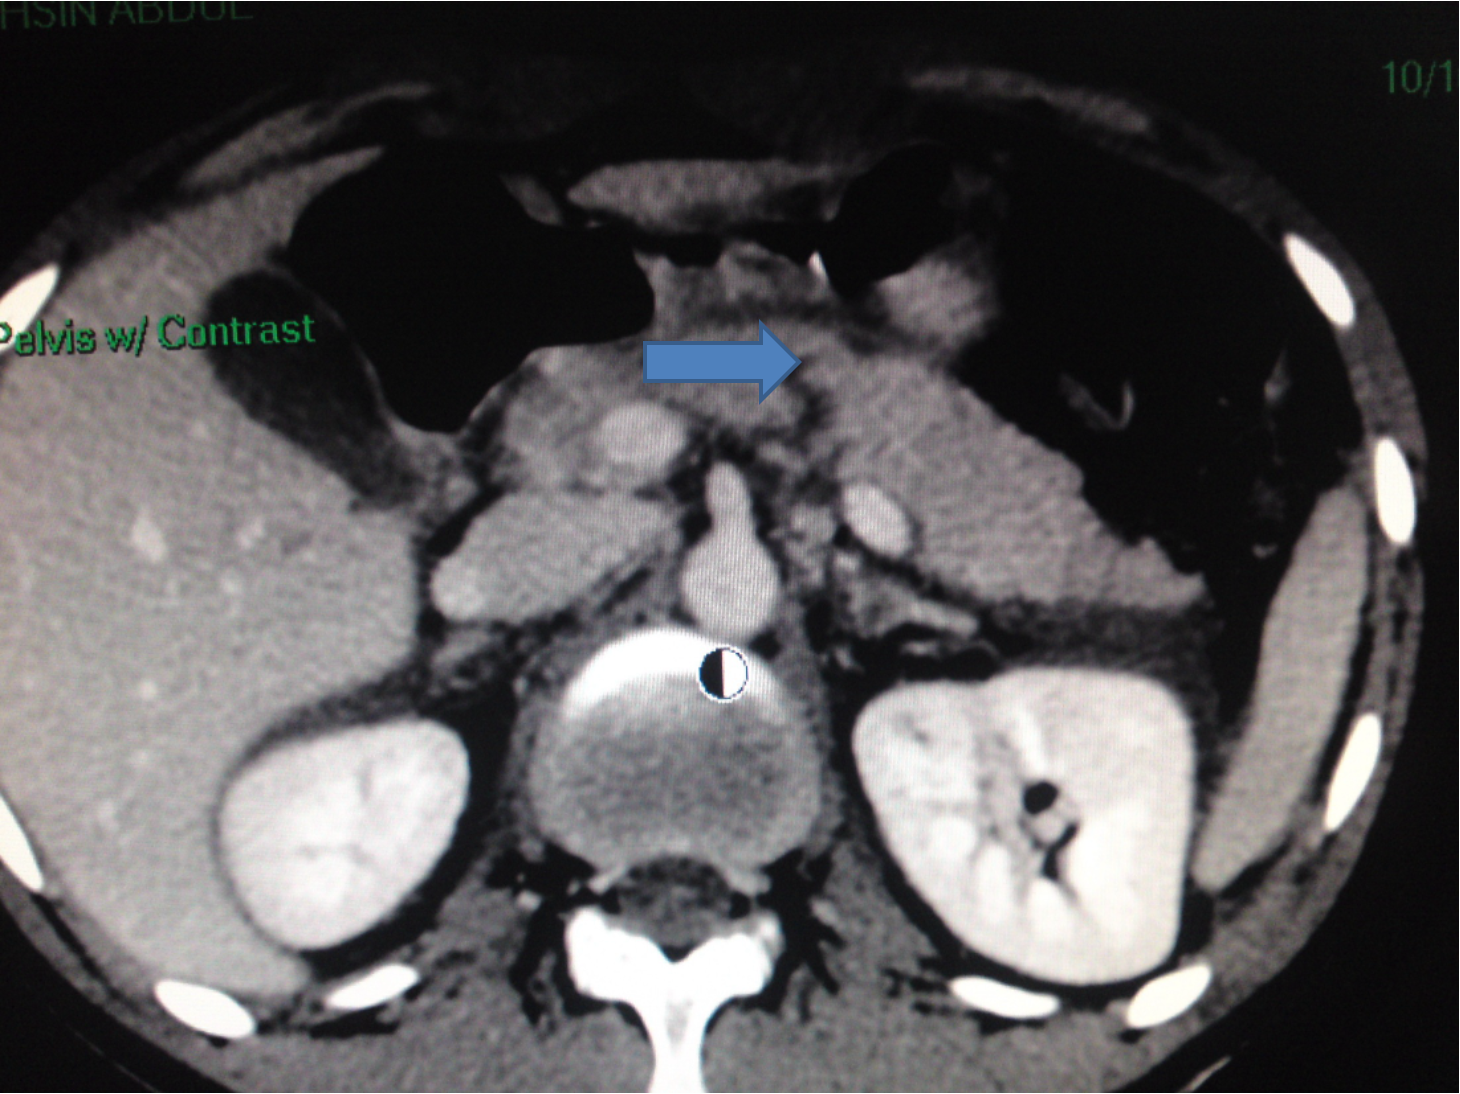

Pancreatic injuries

Diagnosis: difficult

- U/S, CT scan, elevated serum amylase may help